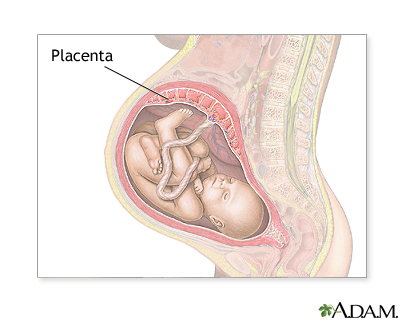

Placenta previa is a problem of pregnancy in which the placenta grows in the lowest part of the womb (uterus) and covers all or part of the opening to the cervix.

During pregnancy, the placenta moves as the womb stretches and grows. It is very common for the placenta to be low in the womb in early pregnancy. But as the pregnancy continues, the placenta moves to the top of the womb. By the third trimester, the placenta should be near the top of the womb, so the cervix is open for delivery.

Sometimes, the placenta partly or completely covers the cervix. This is called a placenta previa.

There are different forms of placenta previa:

- Marginal: The placenta is next to the cervix but does not cover the opening.

- Partial: The placenta covers part of the cervical opening.

- Complete: The placenta covers all of the cervical opening.